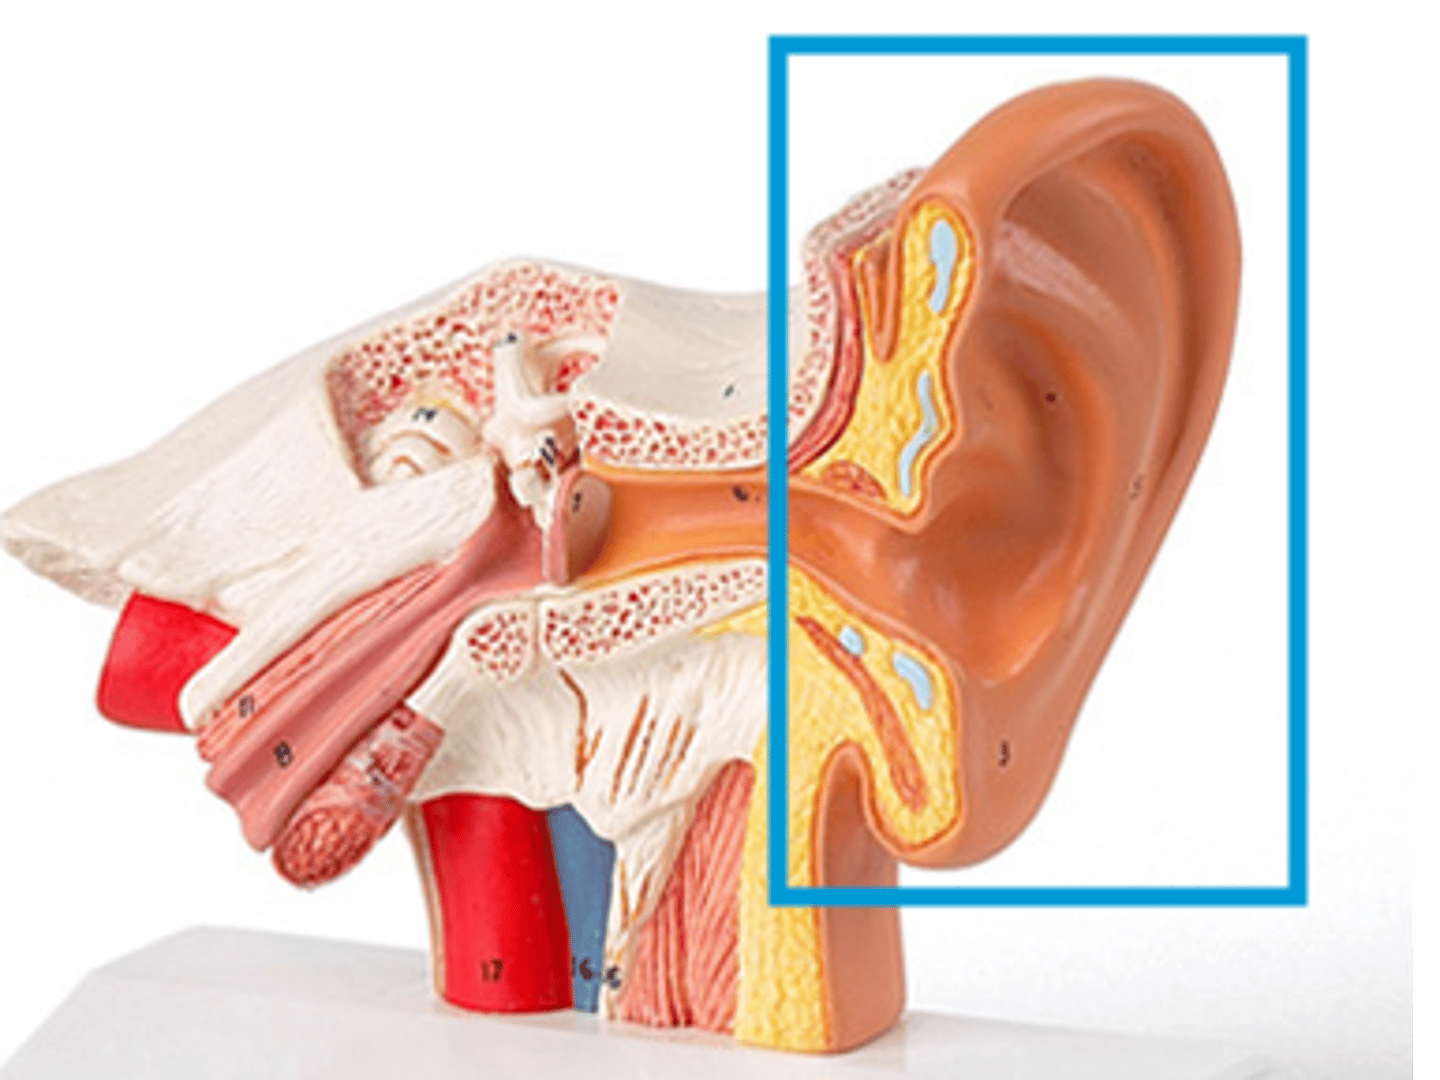

auditory tube

auricle (pinna)

external auditory canal

labyrinth (osseous + membranous)

(general structure, ignore arrow)

temporal bone

tympanic membrane